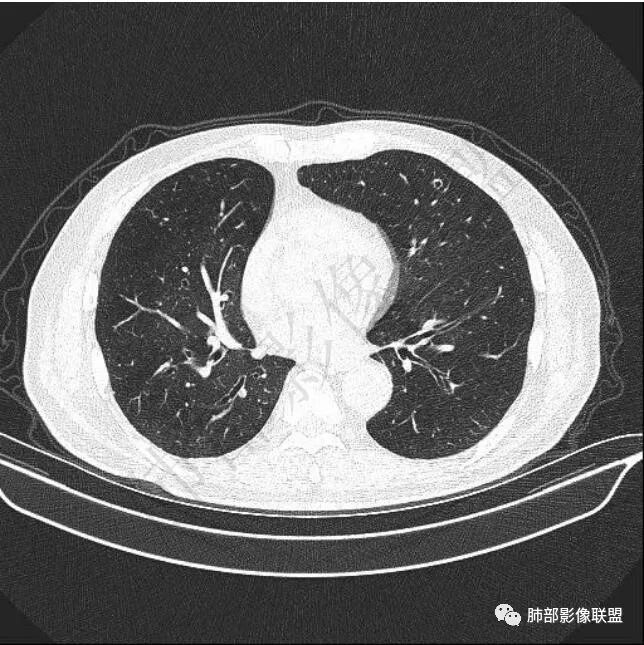

二..发现左肺上叶舌段实性密度小结节影,不规则略呈半环形,边界清楚,未见分叶、毛刺及磨玻璃晕。未见卫星病灶。

9个月后病灶明显增大,边缘较平直,部分膨隆,锁扣样外观,仍旧缺乏典型深分叶及张力,未见胸膜凹陷。

再1个多月后病灶继续增大,较明显不均匀强化,肺门一侧见低密度区。病灶边缘相对不清,可见毛刺。

三.病程脉络相当清楚,即病灶进行性增大,易想到新生物或转移瘤,但经验上分析增长速度显然太快,尤其是对于原发肺腺癌或者肺鳞癌而言,单发转移瘤也较少这样的进展速度。